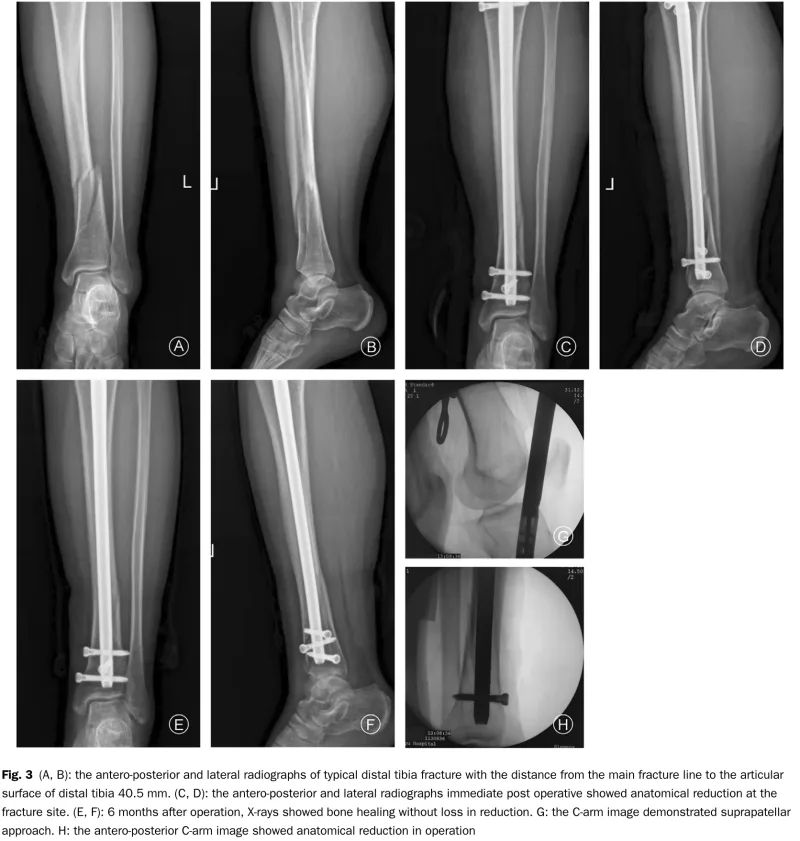

13時半から, 若年成人の脛骨骨幹部骨折に対する髄内釘固定術を執刀しました.